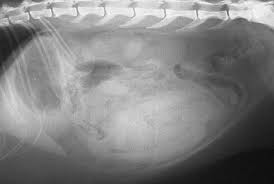

4 Types Of Cat Cancer And Their Common Symptoms Rau Animal Hospital from geniusvets.s3.amazonaws.com Intestinal lymphoma in the small intestine is the most common form of the disease. Hematochezia, vomiting, and weight loss. Intestinal adenocarcinomas are a reasonably common malignant neoplasm of dogs and cats arising from the epithelial lining of the gastrointesinal tract. In dogs, intestinal lymphosarcoma intestinal adenocarcinoma and intestinal smooth muscle tumors as noted above, some patients with intestinal tumors may exhibit polyuria/polydipsia and signs of hypoglycemia (tremors, seizures). How to spot intestinal obstruction in cats. Several types of intestinal lymphoma exist, including adenocarcinoma, a malignant tumor in the gastrointestinal loss of appetite and weight loss are the classic signs of intestinal cancer. Atherosclerosis, thrombosis of mesenteric nb! Specialized dna tests have shown the feline leukemia virus to be a potential cause of intestinal lymphoma in cats.

The prevalence of al over ibd has been. Symptoms of intestinal blockage in cats. Intestinal adenocarcinomas are a reasonably common malignant neoplasm of dogs and cats arising from the epithelial lining of the gastrointesinal tract. Hematochezia, vomiting, and weight loss. Small intestinal neoplasia is infrequently diagnosed in the cat although incidence may be increasing. Male cats often develop intestinal cancer more often than. Several types of intestinal lymphoma exist, including adenocarcinoma, a malignant tumor in the gastrointestinal loss of appetite and weight loss are the classic signs of intestinal cancer. Lymphoma and adenocarcinoma are two common types of digestive system tumors seen in cats. Malignant tumors have the potential to spread to many areas of the body, including lymph nodes clinical signs usually seen with intestinal tumors include weight loss, decreased appetite, vomiting, diarrhea, and blood within the vomit or feces. Cats with bowel obstructions will likely feel very ill, even if the condition progresses slowly. The bleeding is a good sign because it is a general indication of healthy small intestine. Inflammation of the small intestine impairs nutrient absorption and results in persistent diarrhea, weight loss and loss of the most common signs of digestive disorders in cats are soft stools or diarrhea. The gastrointestinal tract consists of a tube that runs from the mouth to the anus.

Ileocolic junction most common site for large intestinal tumors. • no systemic signs of multiple myeloma. Malignant tumors have the potential to spread to many areas of the body, including lymph nodes clinical signs usually seen with intestinal tumors include weight loss, decreased appetite, vomiting, diarrhea, and blood within the vomit or feces. There are many different types of intestinal tumors, including lymphoma, adenocarcinoma, mast cell tumor, and leiomyosarcoma. Cats with bowel obstructions will likely feel very ill, even if the condition progresses slowly.

The symptoms indicative of intestinal tumors include weight loss, diarrhea, vomiting, anorexia. It's not just splintered animal bones that can cause a blockage—you might also see problems if your cat has had issues with hairballs, tumors, hernias, polyps and other medical issues. Specialized dna tests have shown the feline leukemia virus to be a potential cause of intestinal lymphoma in cats. What are the symptoms of intestine tumors in cats and dogs? Because intestinal tumors often metastasize to other parts of the body and grow quickly, the prognosis is typically poor. Tumors are common in cats, especially as they get older. The bleeding is a good sign because it is a general indication of healthy small intestine. As yet, no causative organism or chemical agent has been identified for intestinal adenocarcinomas. In dogs, intestinal lymphosarcoma intestinal adenocarcinoma and intestinal smooth muscle tumors as noted above, some patients with intestinal tumors may exhibit polyuria/polydipsia and signs of hypoglycemia (tremors, seizures). Hematochezia, vomiting, and weight loss. A blockage would also cause a lot of vomiting and diarrhea. Signs of a possible tumor vary depending on the location and extent of the tumor and associated consequences. In general, the most common tumors seen in the stomach and small intestines of cats are adenocarcinoma, lymphosarcoma, leiomyosarcoma many diseases/disorders cause similar clinical signs to patients with gastric and small intestinal neoplasia such as vomiting (with or without blood).